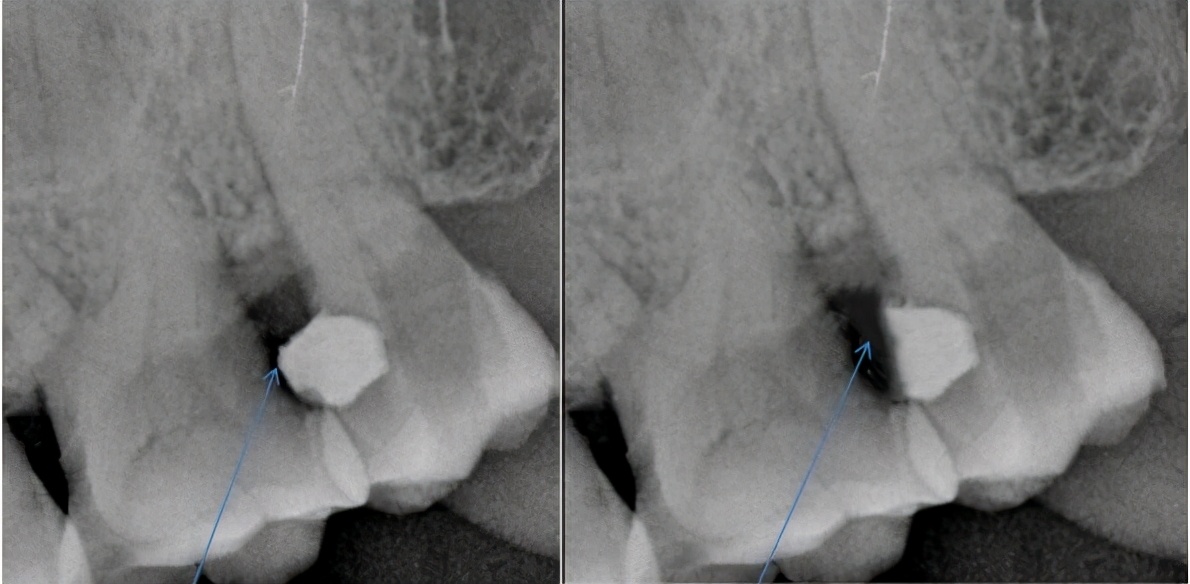

(3)邻面龋充填后敏感,可拍摄患牙区的小牙片,看看是否有相邻区域的牙齿还有未发现的龋坏,也可顺便检查一下充填物是否有悬凸或者未充填到位的地方,若有,及时处理便可解决问题。